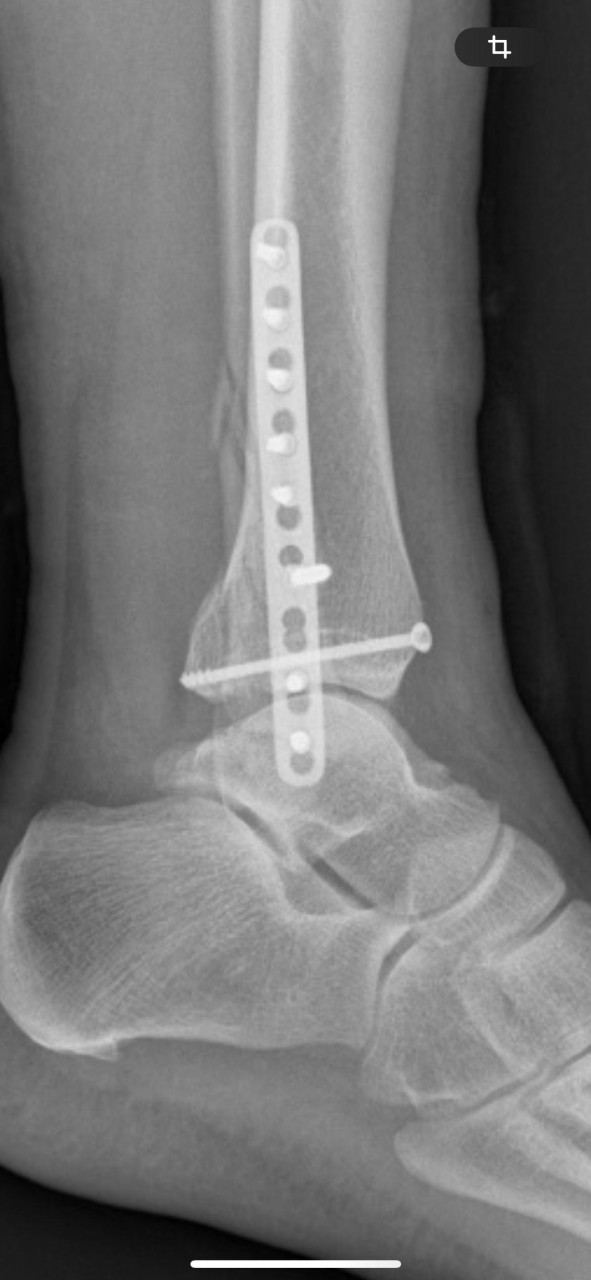

Сегодня, спустя 7 недель, сделал контрольный снимок голеностопа. Прикладываю снимки после оперрации и спустя семь недель. Хочу узнать ваше мнение. Можно начинать лфк, начинать приступать на ногу?

3. Спустя 7 недель https://iimg.su/i/Be028n

4. Спустя 7 недель https://iimg.su/i/8T1HpG

Здравствуйте. По контрольному снимку через 7 недель конструкция стабильна, видно начало консолидации. Можно постепенно начинать щадящую ЛФК (пассивные и активные движения, изометрические упражнения) и опираться на ногу частично в ортезе, полную нагрузку можно после 10-12 недель и повторного контроля. Каждый случай индивидуален, и без очного осмотра точную рекомендацию дать сложно. Поэтому обратитесь к своему ортопеду, для точной оценки.